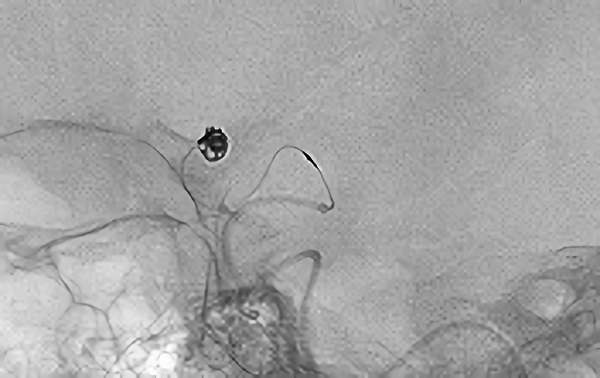

No.1628 手術中